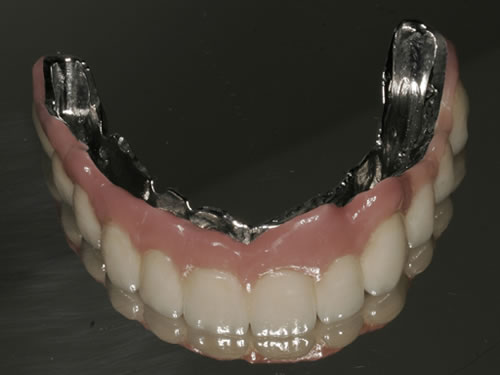

Diese Beispiele ließen sich endlos fortführen. Sie zeigen die Probleme bei der Versorgung zahnloser Kiefer, wie sie immer wieder geschildert werden. Mit Hilfe sehr einfacher Maßnahmen kann durch die Einpflanzung künstlicher Zahnwurzeln eine instabile Prothese soweit befestigt werden, dass die Kau- und Sprechfunktion wieder hergestellt ist. Manchmal kann die alte Prothese weiterverwendet werden, in dem man in die Prothesenbasis Sekundärteile einarbeitet, die für Halt sorgen (Abb. 3.5, 3.6). Bei aufwendigeren Steg- oder Teleskoparbeiten muss auch der Zahnersatz der auf den Implantaten fixiert wird neu angefertigt werden. Diese Arbeiten werden dann brückenartig und sehr grazil gestaltet. (Abb. 3.7 bis 3.12).

Abb. 3.9: Prothesenansicht von unten mit grazil eingearbeiteten Halteelementen.